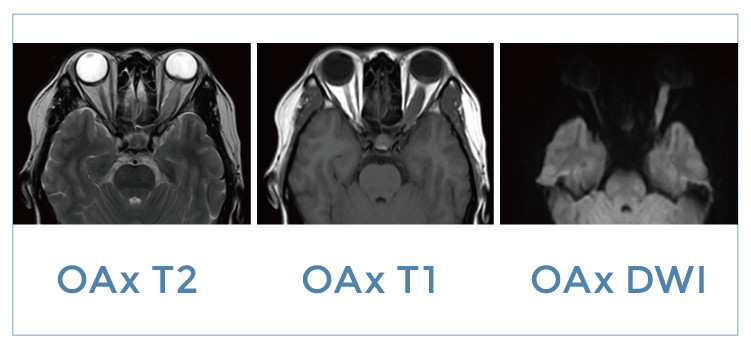

【朗润影像档案】20191108磁共振影像病例结果讨论

【朗润影像档案】磁共振影像病例分享(编号20191108)